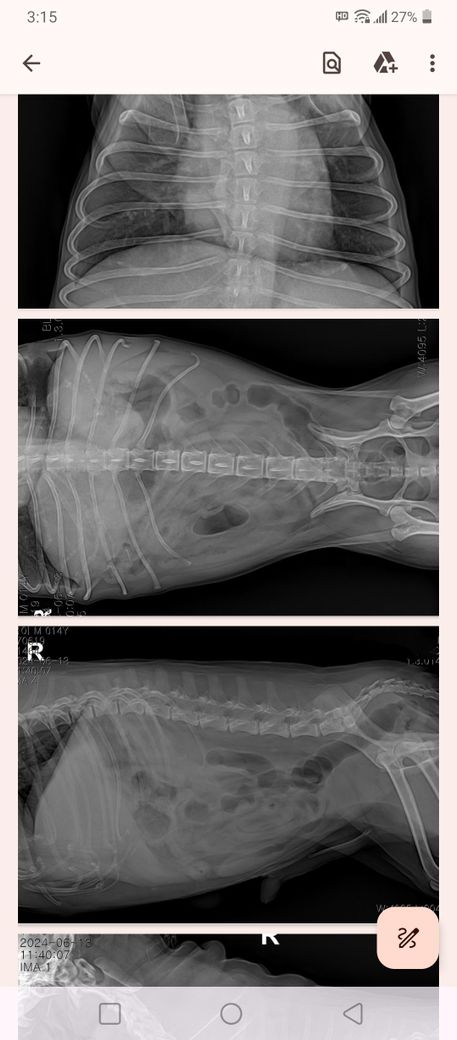

액스레이 사진인데 간이 작은 걸까요.?

강아지 간혈관기형 있어 간 크기가 작고,

좌측에 4~5cm 간종양과 간엽절제를 하면 남는 간의 크기가 적어서 수술이 힘들다고 합니다.